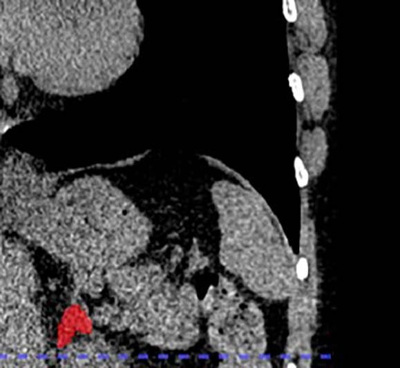

Lead author of the new study, Dr. Elena Ghotbi, developed and trained a deep learning model to measure adrenal gland volume on existing CT scans.

(Elena Ghotbi, M.D., and RSNA via SWNS)

The team applied their deep learning model to the CT scans to segment and calculate the volume of the adrenal glands.